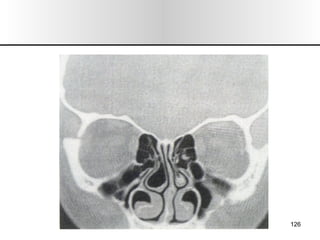

EXPLORACION 1.- Inspección/ Palpación:  Forma, color, alt. Dermicas, movilidad, dolor, inspiración forzada (colapso alar). 2.- Rinoscopia Ant: Desvios, esporones, cornetes, polipos  (solitario),  secreciones, perforaciones, CE, tumores. 3.- Rinoscopia Post: Hipertrofia cornetes, tumores. 4.- Tacto de Cavum: Adenoides. 5.- Rinonanometria: Dif de presión entre vestíbulo y coanas, flujo de vol. 6.- Exp. Radiológica : mentonasoplaca, frontonasoplaca, perfil, axial de Hirtz o submentovertex. TAC, RMN. 7.- Endoscopia Rinusinusal. 8.- Pruebas Alergologicas: pruebas cutaneas, eosinofilia, exudado nasal. SEMIOLOGIA

EXPLORACION 1.- Inspección/Palpación: Forma, color, alt. Dermicas, movilidad, dolor, inspiración forzada (colapso alar). 2.- Rinoscopia Ant: Desvios, esporones, cornetes, polipos (solitario), secreciones, perforaciones, CE, tumores. 3.- Rinoscopia Post: Hipertrofia cornetes, tumores. 4.- Tacto de Cavum: Adenoides. 5.- Rinonanometria: Dif de presión entre vestíbulo y coanas, flujo de vol. 6.- Exp. Radiológica : mentonasoplaca, frontonasoplaca, perfil, axial de Hirtz o submentovertex. TAC, RMN. 7.- Endoscopia Rinusinusal. 8.- Pruebas Alergologicas: pruebas cutaneas, eosinofilia, exudado nasal. SEMIOLOGIA